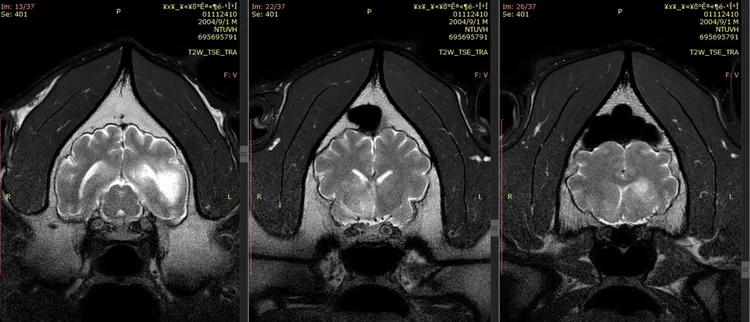

根據動物園公布的第2次MRI(磁振造影)影響,發現團團腦部病變病灶區域明顯擴大,且還出現腫塊效應,園方指出惡性腫瘤機率大幅提高,但因未能以侵入性切片檢查無法百分之百確認。

團團進行第二次MRI檢查時,對麻醉反應、甦醒恢復時間皆延長。鄭秋虹還原就醫狀況,指團團第一次檢查時麻醉完10幾分鐘就醒來,第二次雖有醒來但回去仍昏昏沉沉,並說「團團真的不能再經一次風險」。

賴燕雪補充,通常動物進行治療時,醫生也會監看各種數值,但團團這次麻醉後心跳、呼吸次數明顯變慢,也代表身體狀況不好、無法正常代謝藥物,顯現藥物劑量對牠來說已經太重了。

賴燕雪進一步說,團團的腦部MRI影像顯示有水腫,現除給予抗癲癇藥物,也有消水腫的藥物,當腦部腫塊壓迫不那麼明顯時正常功能也會回歸,「這時團團讓不舒服的臨床症狀就會較少。」